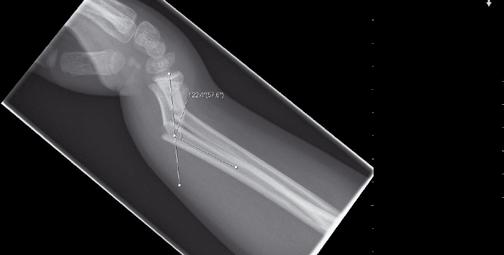

På onsdagsmorgonen gick Yngvar Krukhaug, Bergen, på ett didaktiskt sätt igenom eviden sen för olika behandlingsstrategier av distala radiusfrakturer. ”Take home message” blev att de data vi grundar våra beslut på generellt är av undermålig kvalité, att gipsbehandling kan användas i 80 % av fallen och att det nu finns evidens för användning av volar plattfixation vid instabila AO C1 och C2 frakturer. Vid mer splittrade frakturer finns inga data som visar att volar platta är bättre än externfixation, nå got som ytterligare diskuterades vid efterföl jande symposium om indikationer för vinkel stabila plattor med Ingvar Allvin, Örebro, som moderator.

Knud Stenild-Christensen, Aalborg, redovisade på torsdagsmorgonen sina erfarenheter av motoriserade märgspikar vid benförlängning. Metoden måste fortfarande anses som experimentell kirurgi då endast fem personer i Europa och Australien via firman har fått körkort att använda metoden.

Metoden introducerades 2003 och första fallpublikationen presenterades 2005, så hittills finns mycket begränsad evidens för spikens effektivitet. Teoretiskt är dock metoden spännande, med en dynamisk märgspik som via en elektrisk sändare som hålls mot huden styr distraktionen av den teleskoperande spiken. Med endast tre 90 sekundersstimuleringar per dag styr patienten distraktionen, en metod som i motsats till Illizarovtekniken inte ger upphov till smärtor. Patienterna kan även direkt belasta fullt och komplikationerna, även om de är av samma typ som vid Illizarovtekniken, är enligt Stenild färre än tidigare. Nu pågår en ytterligare utveckling av ”Fitbone spiken” där man datoriserat metoden för att erhålla ”feed back” på krafter och belastningar som uppkommer, något som sen gör att man än bättre kan styra förlängningen. Framtiden får utvisa om detta är en dagslända eller ett instrument som kommer att spridas till en större grupp ortopeder.